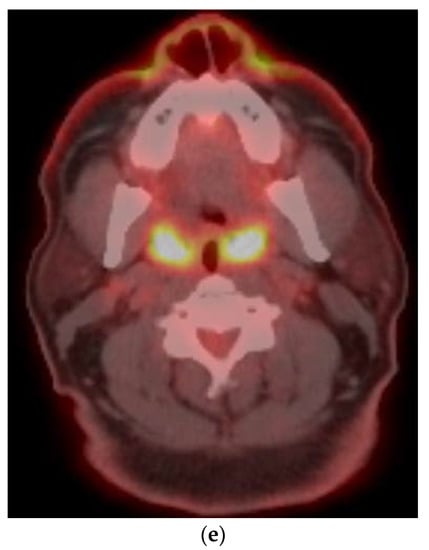

8.2. Response Assessment

9. Disease Monitoring